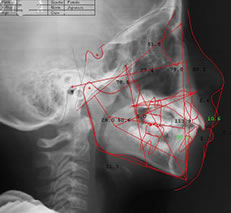

矯正治療は歯だけではなく、顎などお口全体のバランスを考えて行う必要があります。当院では、セファロレントゲンやCTを駆使し、精密な診断を行っています。

特にセファロレントゲンは頭部の側面や正面から撮影する特殊なX線写真で、矯正治療前の診断に欠かせない装置です。